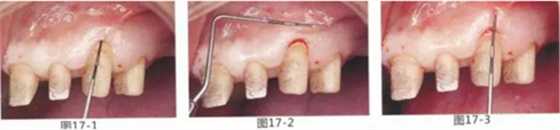

圖17-1~3 左上3的牙周袋探測值為3mm,角化牙齦寬度為2mm。也就是完全不存在附著齦,如果這種狀態(tài)下佩戴修復(fù)體的話,很有可能發(fā)生頸部暴露等問題。

圖17-4 左上1,2進行齦瓣根尖側(cè)轉(zhuǎn)移,左上3,4進行游離牙齦移植,在去除牙周袋的同時獲取附著齦。

圖17-5 牙周治療完成后的正面照。左上3,4部位處游離齦移植片的上端通過骨膜縫合固定在頰側(cè)嵴頂部。這樣可以使其愈合效果與齦瓣根尖側(cè)轉(zhuǎn)移相同。